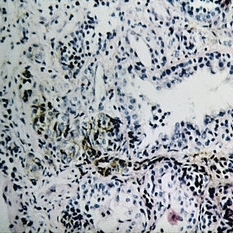

Slide 7-29

Feb 25 2019 by Lancaster Course in Ophthalmology

Benign lymphoid hyperplasia of the conjunctiva may resemble a normal lymph node.

Condition/keywords: conjunctiva, hyperplasia, lymph node